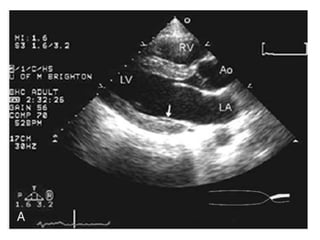

Apical four-chamber view recorded in systole in a normal patient

Apical four-chamber viewrecorded in systole in a normal patient

• #25 Para sternal long axis view . Note the anterior and posterior mitral valve leaflets. The posterior leaflet lies against the inferoposterior wall of the left ventricle (LV) (arrow) and may not be clearly seen when fully open.

• #26 Both leaflets have moved toward the center of the left ventricular cavity and have closed with a

• #27 Apical four-chamber view recorded in systole in a normal patient. In this image, the normal closure pattern of the anterior and posterior leaflets of the mitral valve is clearly demonstrated. At the upper right, the closure pattern has been expanded. Note that the anterior and posterior mitral valve leaflets do not close tip to tip but rather along a 4-mm length [the zona coapta (ZC)].